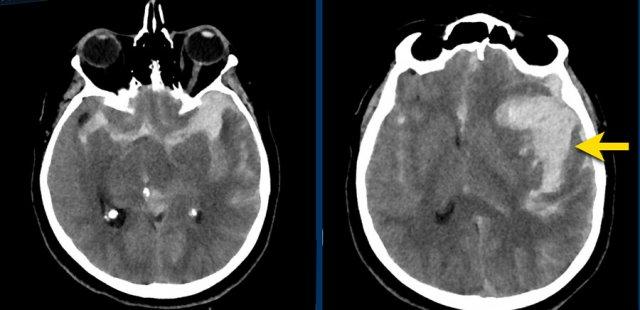

Nhồi máu với chuyển dạng xuất huyết

Xuất huyết thùy não trong nhồi máu xuất huyết

Bệnh nhân này nhập khoa cấp cứu với triệu chứng liệt nửa người trái và rối loạn vận ngôn.

Các triệu chứng nhanh chóng thuyên giảm và khi các bác sĩ quyết định cho bệnh nhân xuất viện, các triệu chứng đột ngột tái phát.

Bệnh nhân được chẩn đoán nhồi máu não cấp tính trong vùng phân bố của động mạch não giữa phải.

Liệu pháp tiêu huyết khối được bắt đầu ngay lập tức.

Ngày hôm sau, tình trạng bệnh nhân xấu đi và CT-scan lần hai cho thấy hình ảnh nhồi máu xuất huyết diện rộng trong vùng phân bố của động mạch não giữa phải.

Bệnh nhân tử vong vào ngày hôm sau.

Bệnh nhân này được nhập vào đơn vị đột quỵ với chẩn đoán nhồi máu não mới trong vùng phân bố của động mạch não giữa trái.

Do đến viện muộn, ngoài cửa sổ điều trị tiêu huyết khối, bệnh nhân không được chỉ định liệu pháp này.

CT không tiêm thuốc cản quang (NECT) tái khám (hình A) được chỉ định do tình trạng lâm sàng xấu đi, cho thấy vùng giảm tỷ trọng giới hạn rõ trong vùng phân bố của động mạch não giữa trái. Trong vùng giảm tỷ trọng này, ghi nhận các ổ tăng tỷ trọng nhỏ, mờ nhạt.

MRI thực hiện vài giờ sau trong cùng ngày cho thấy các ổ xuất huyết (mũi tên) phù hợp với hình ảnh chuyển dạng xuất huyết dạng chấm xuất huyết (petechial) của ổ nhồi máu thiếu máu cục bộ.